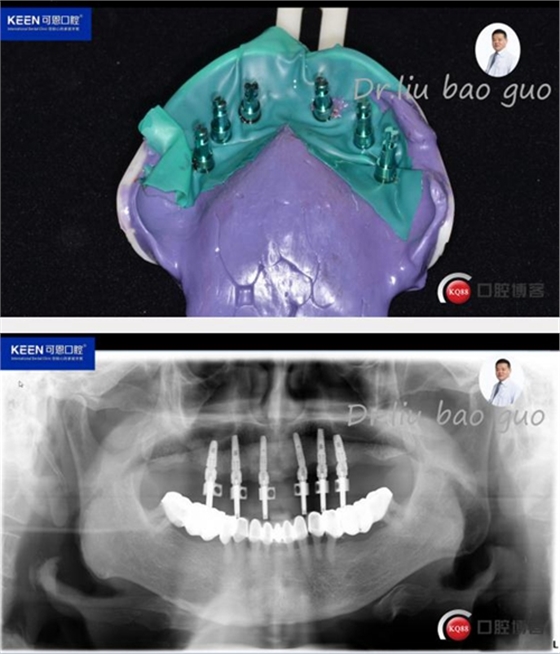

數(shù)字化種植導(dǎo)板設(shè)計(jì)及制作

手術(shù)過(guò)程

(因設(shè)備限制,未能實(shí)現(xiàn)手術(shù)全程數(shù)字化導(dǎo)板,僅在手術(shù)之前導(dǎo)板定位)

術(shù)后照片

種植后開(kāi)始進(jìn)行取模,制作義齒